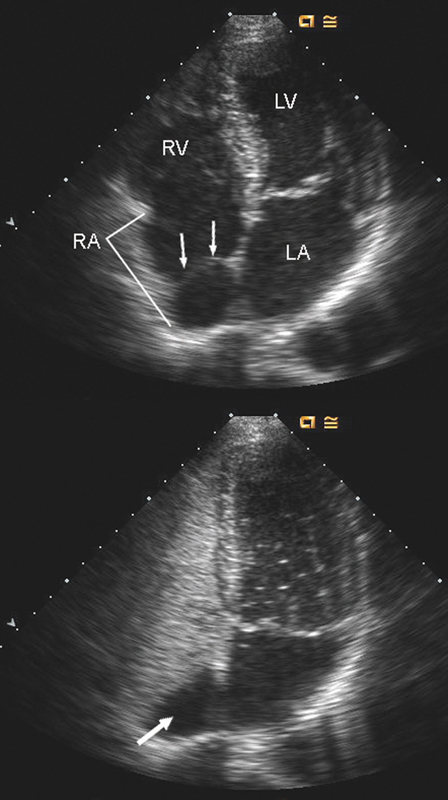

فحوصات تشخيصية لبعض امراض القلب والشرايين التاجية